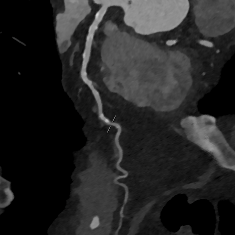

Hier entlarvt die multiplanare Rekonstruktion eine hochgradige Stenose des RIVA Hier entlarvt die multiplanare Rekonstruktion eine hochgradige Stenose des RIVA © Privatdozent Dr. Andreas Rolf, Kardiologie am Herzzentrum, Kerckhoff-Klinik, Bad Nauheim